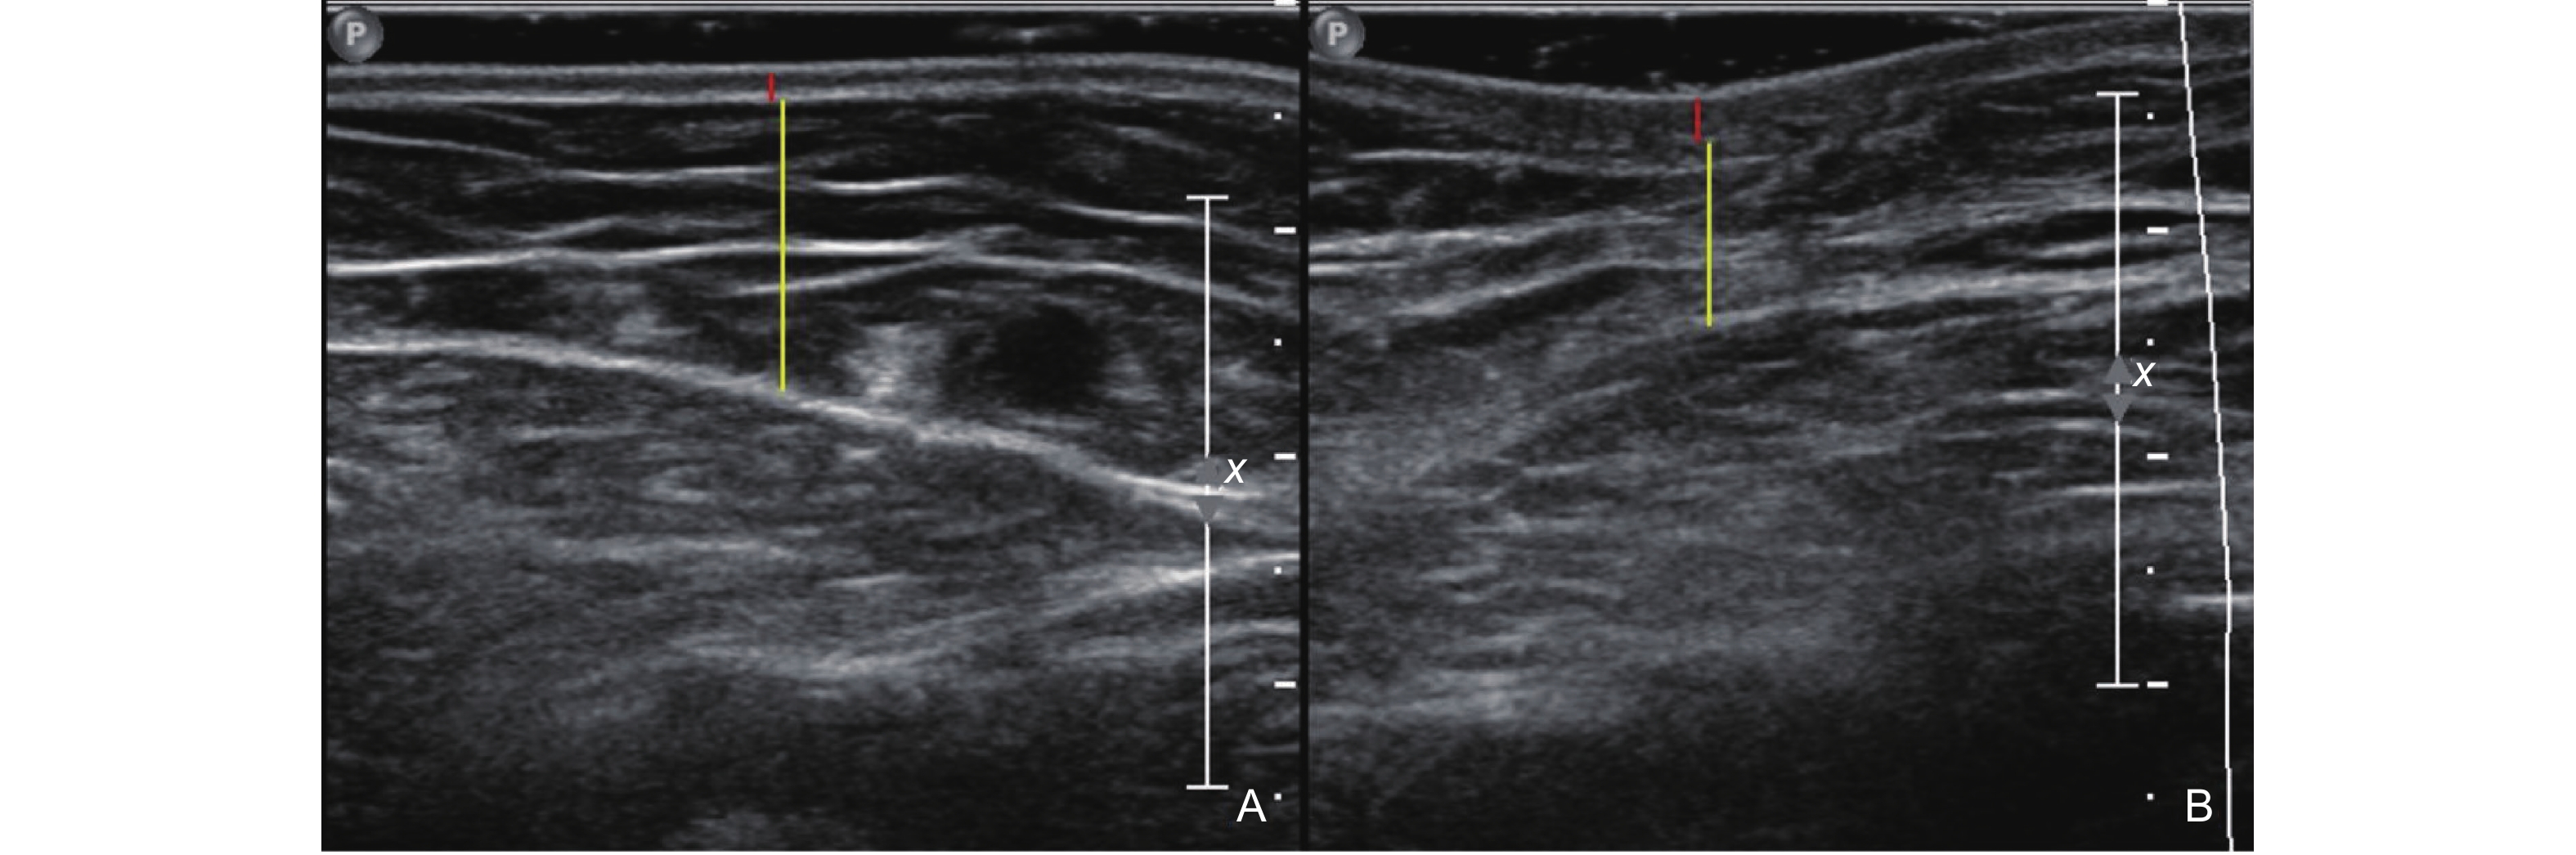

Figure 3

Clinical [47] and ultrasound manifestations of port-wine stains. (A) Pink type of PWS; (B) Purple type of PWS; (C) Thickening type of PWS; (D) Comparison of gray-scale ultrasound between the PWS lesion and the healthy side; (E) The blood flow signal at the lesion site of PWS increases."

| [47] | Xiang Xi , Zhang Lingyan , Zhong Lin , Gao Yi , Qiu Li . Multimodal ultrasound manifestations of port-wine stains and their application in efficacy assessment of photodynamic therapy. Chinese Journal of Dermatology 2024; 57: 801-806 |